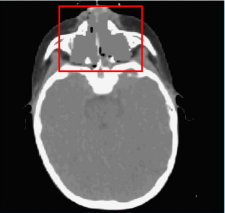

The case of a treatment with fields crossing the nasal cavity has been taken into consideration. The field directions of the nominal plan are shown in Fig.3; the frontal fields F1 and F2 encounter the nasal cavity to reach the target volume. To evaluate the stability of the IMPT plan, first, the original CT image was modified to simulate the extreme scenarios, of the cavity being completely empty (HU = 0) and filled with mucus (HU similar-to-or-equals\simeq 30), as shown in Fig.4; the original plan (PLAN-NOM) and the plan with OL penalization (PLAN-OL), where an OL (0,1)absent01\in(0,1) was selected for the nose VOI, were re-computed for both extreme scenarios, to evaluate the potential variation range with respect to the planning CT. We named PLAN-NOM-H and PLAN-NOM-L, respectively, the difference between the nominal plan recomputed on the CT with low and high density nasal cavity and the plan computed on the original CT and we did similarly for the extreme scenario plans with OL penalization (PLAN-OL-H and PLAN-OL-L).

(a) Axial CT slice

(b) Azimuthal CT slice

Figure 3: Fields crossing the nasal cavities: axial and azimuthal CT slice of the nasal cavity plan showing the red contour of the PTV; the fields F1, F2 and F3 involved in the treatment are also shown.